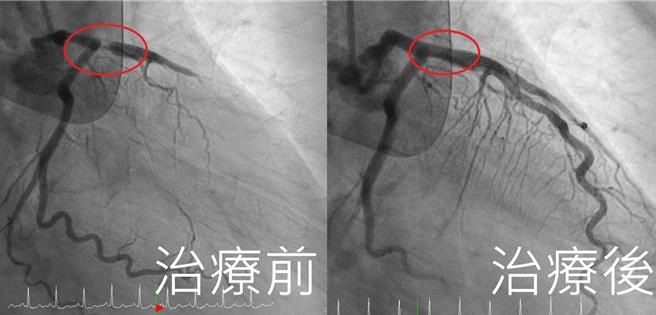

患者經過搶救治療後,成功打通血管。(亞大醫院提供/馮惠宜台中傳真)

由於患者血壓仍不穩定,為穩定血液循環,心臟外科醫師黃俊晟緊急裝置葉克膜維生,之後再轉入心導管室,由王宇澄執行導管檢查,赫然發現患者左前降支冠狀動脈阻塞高達99%,「有如公路斷崖」,屬於極為致命的血管病變,評估後迅速施行冠狀動脈支架置入術,順利打通血管,恢復血流通暢,2小時內成功續命。